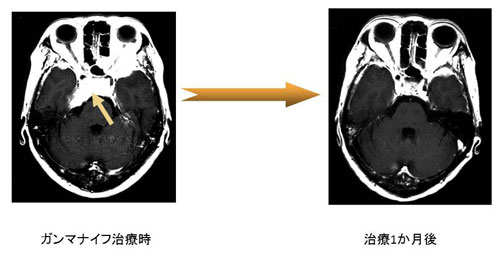

症例3 47歳 乳がんの海綿静脈洞への転移(図5)

図5左MRIの矢印に示す白く造影される部分(右海綿静脈洞)に乳がんからの脳転移を認めました。神経症状として右顔面の激痛、右眼が全く動かない、右視力低下を認めました。ガンマナイフ治療後1か月でこれら神経症状は完全に回復し、左MRIのごとく病巣の著明な縮小を認めました(図5右)。

図5